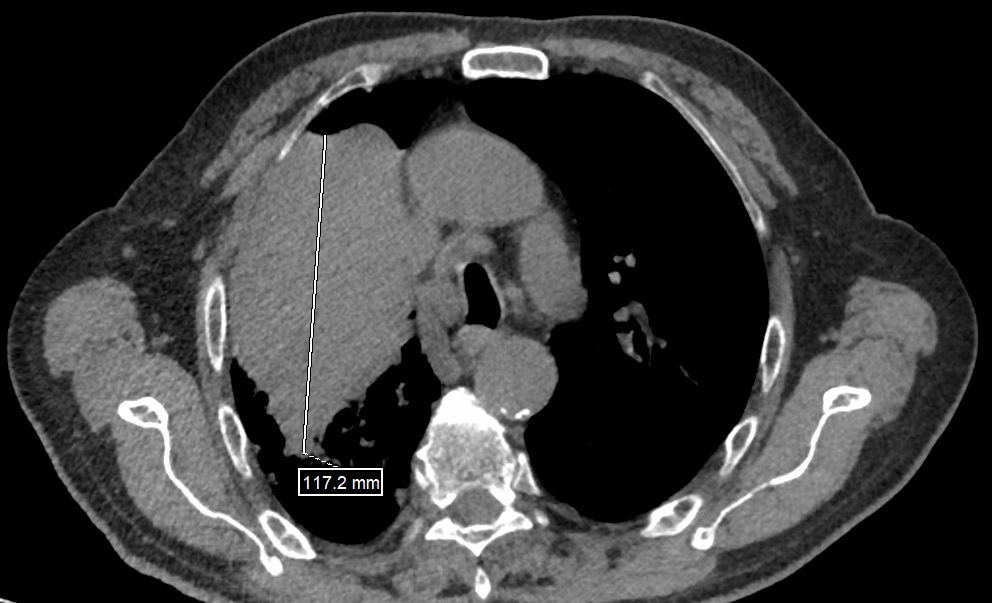

四个月前,70岁的胡大爷因咳嗽、咳痰伴痰中带血,来到江西省肿瘤医院胸外三病区就诊。经CT检查结果显示,其右上肺存在6.5cm×11.7cm大小的肿瘤,经纤维支气管镜活检明确为肺鳞癌,初步评估临床分期为T4N2M0 ⅢB期。

(新辅助治疗前CT)